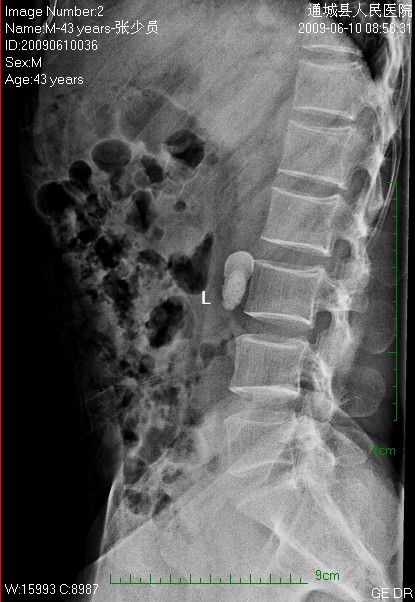

标题: CL1983:尿路结石

这颗石头长得怪,好象有顶帽子戴。

左侧输尿管结石并左肾积水